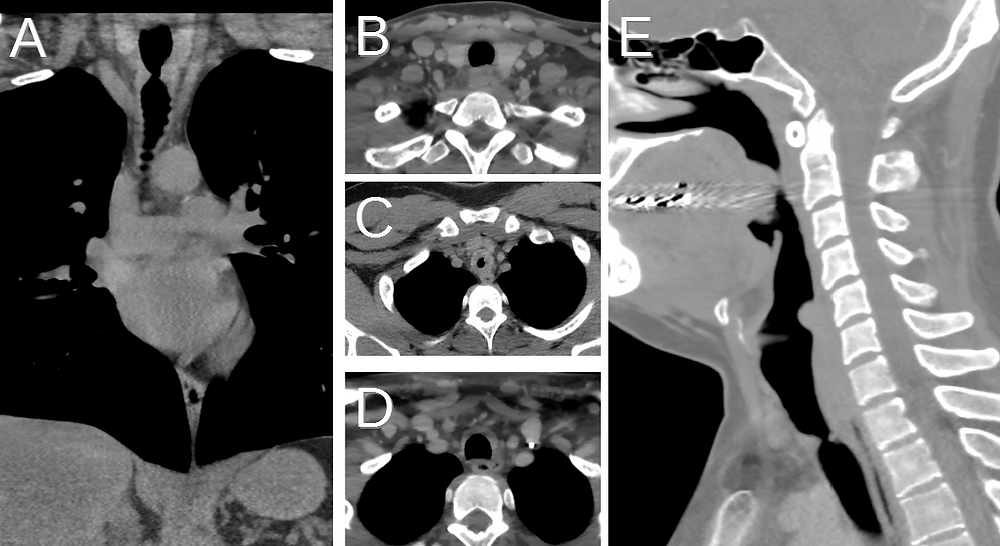

From www.globalradiologycme.com

Post Intubation Tracheal Stenosis Post Intubation Chest Pain Intubation techniques, checking ett position after initial placement, and immediate complications of ett as well as complications. Pneumothorax (look for asymmetrical chest movement) lung collapse (look for If you're having chest pain, take these symptoms seriously. If you have concerns that your pain isn't just due to healing from A study measuring hemodynamic and respiratory variables during endotracheal suctioning showed. Post Intubation Chest Pain.